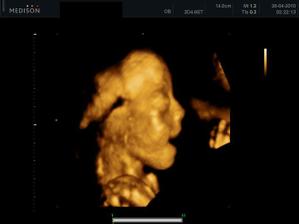

27.04. - (24+5) video, tak z videa nakonec sešlo. Dohodli jsme se s panem doktorem, že se mu ozvu, tak za 14 dní, až Karolínka ještě povyroste. Teď má v bříšku ještě moc místa a nebylo by to úplně ono. Tak jsme alespoň dostali několik foteček a dva doktoři nám potvrdili, že jde skutečně o holčičku.

11.05. - (26+5) dnes jedeme na video

video se povedlo, máme asi 6 cca 5 - 10ti vteřinových videíí.Bylo to super. Karolínka se zase mlela jako drak. Je taková živoučká 😀